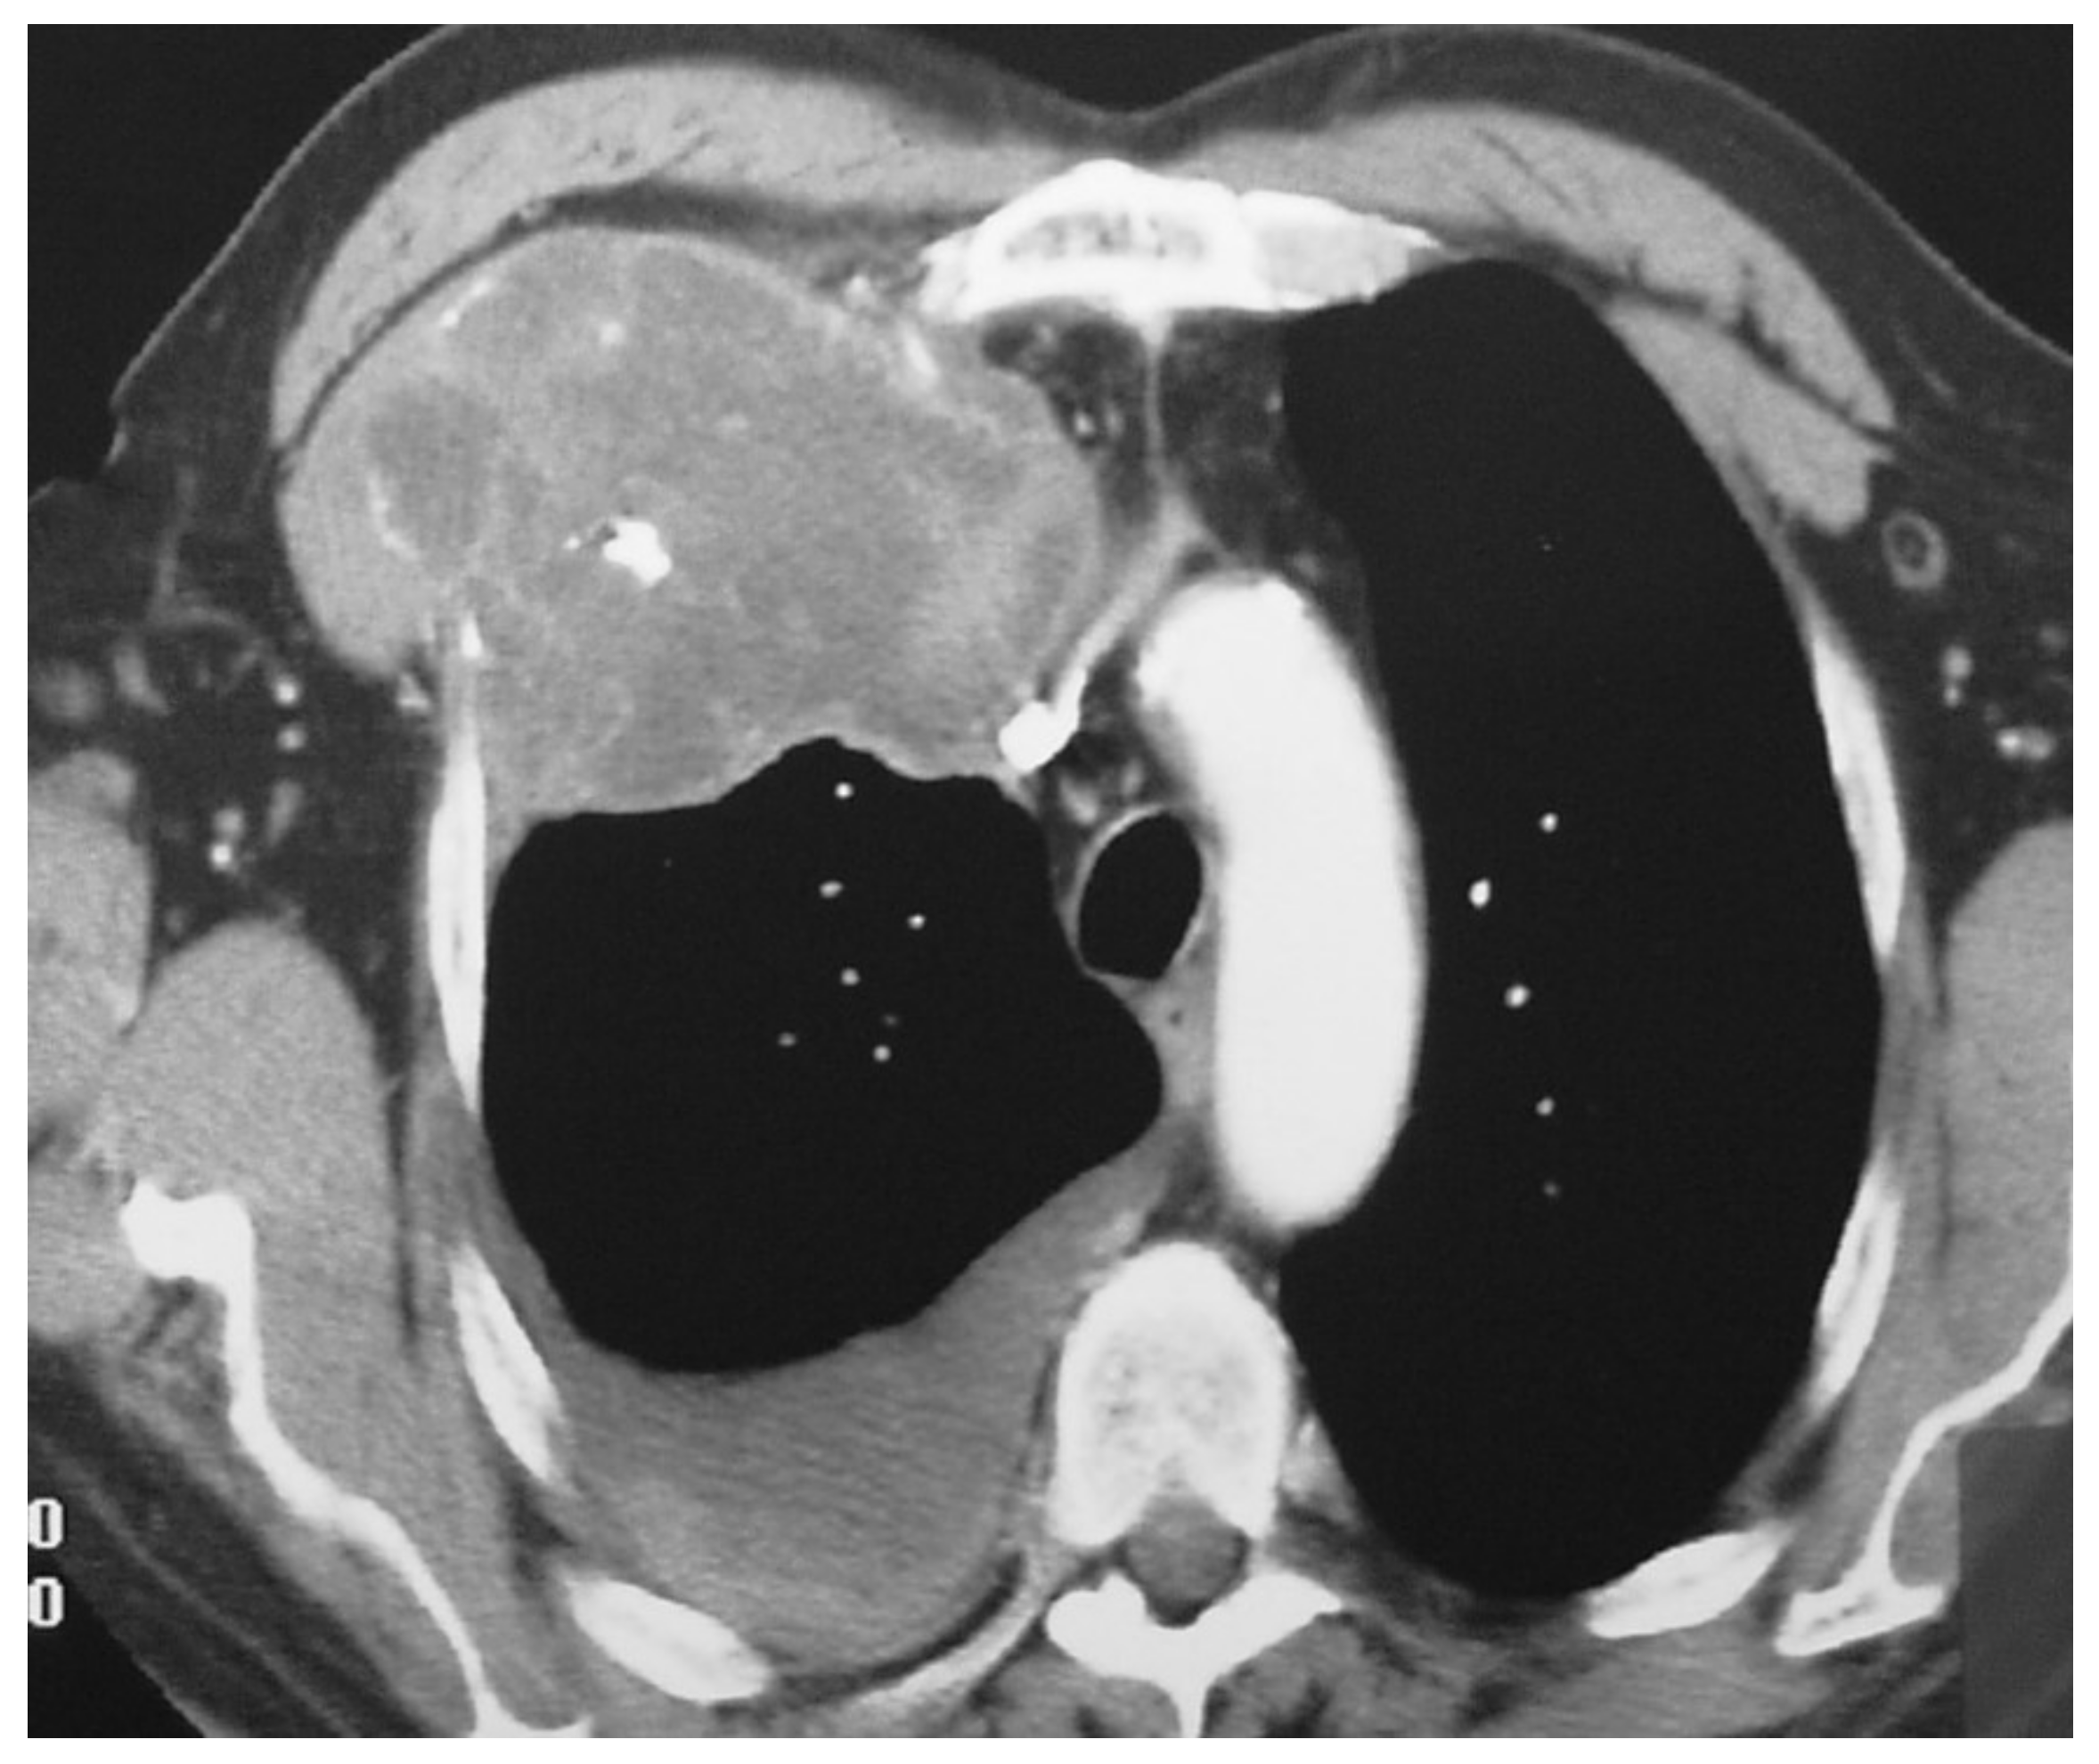

Grade 1 and 2 Chondrosarcomas of the Chest Wall: CT Imaging Features and Review of the Literature

3. Results